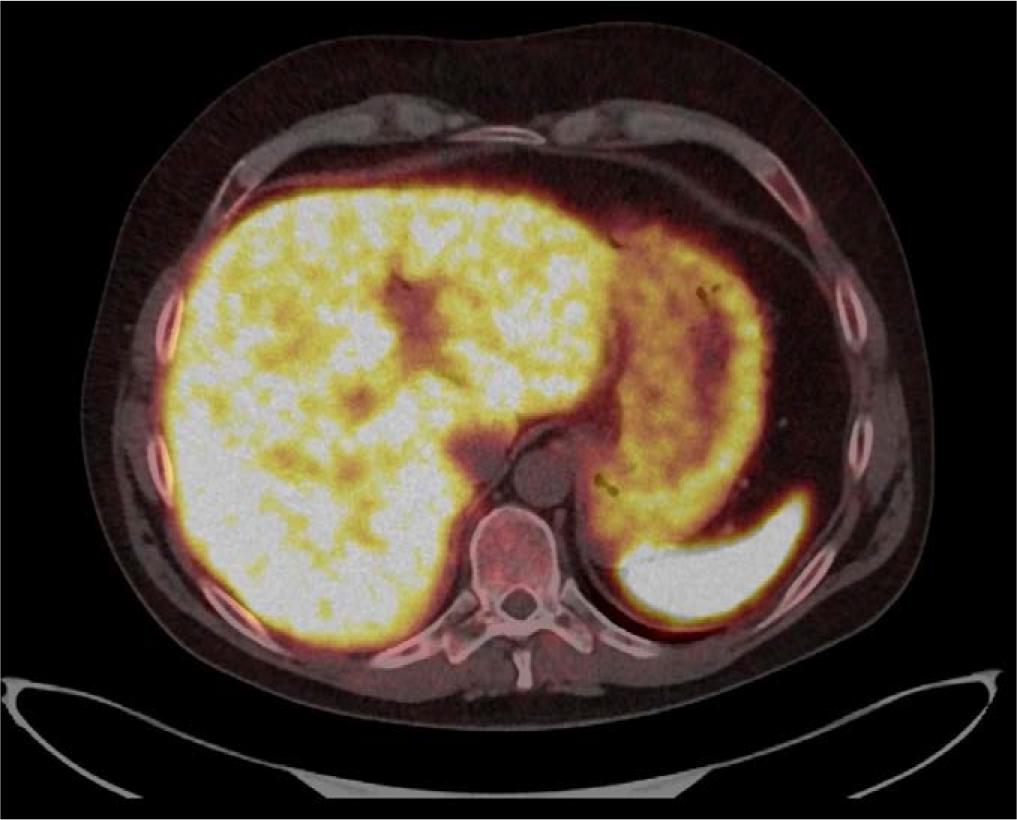

Axial fused [68Ga]Ga-DOTA-TATE PET/CT image at the level of the upper abdomen. Moderately increased radiotracer uptake is visible along the lesser curvature of the stomach near the cardiac orifice. This area corresponds to the gastric wall thickening visualized previously in the MRI, where a 106 × 34 mm lesion was seen. Although the uptake is not significantly intense, its location aligns with the previously identified abnormality. At the time of the MRI, differential diagnoses included gastric lymphoma, hypertrophic gastritis, and Zollinger-Ellison syndrome.